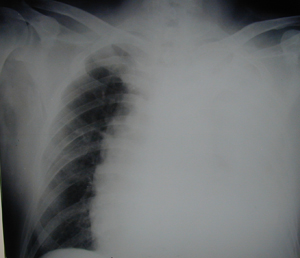

Εικόνα 1

Οπισθιοπροσθία ακτινογραφία θώρακος όπου υπάρχει πλήρης κατάληψη του αριστερού ημιθωρακίου από υγρό που προκαλεί μετατόπιση του μεσοθωρακίου προς την υγιή πλευρά. Ο ασθενής παρουσιάστηκε με έντονη δύσπνοια, και από το ιατρικό ιστορικό του ο ασθενής ανέφερε την λήψη αντιπηκτικών.